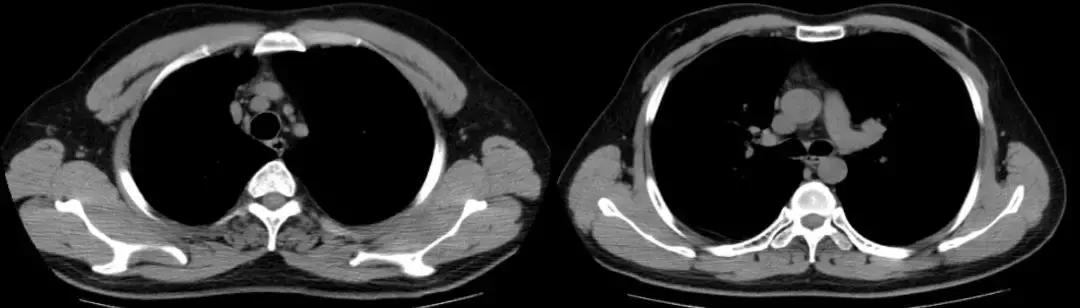

2018-01-22行支气管镜检查:示两侧支气管粘膜充血明显,可见少量白色分泌物,充分吸引;于左下叶生理盐水20ml灌洗2次,回吸收均约10余ml;左上叶、左下叶刷检,刷片共6张。(气管镜报告如下图)。

隆突 右上叶

右中叶 右下叶

左上叶 左下叶